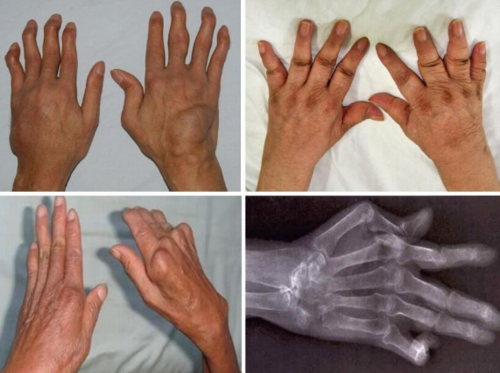

类风湿关节炎图片

类风湿关节炎图片,类风湿图片早期

类风湿关节炎

类风湿手指肿胀图片

类风湿性关节炎肿胀图

类风湿关节炎早期症状